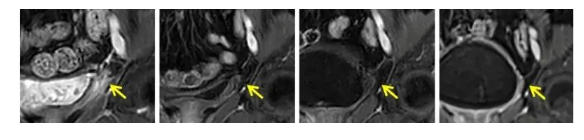

案例1:

一位晚期宫颈癌患者的膀胱内出现了巨大的肿瘤转移灶,但在接受了TIL(肿瘤浸润淋巴细胞)治疗后,仅过了6个月,这些肿瘤竟然全部消失了,实现了完全缓解的状态,并且这种良好的状态持续了整整19个月!